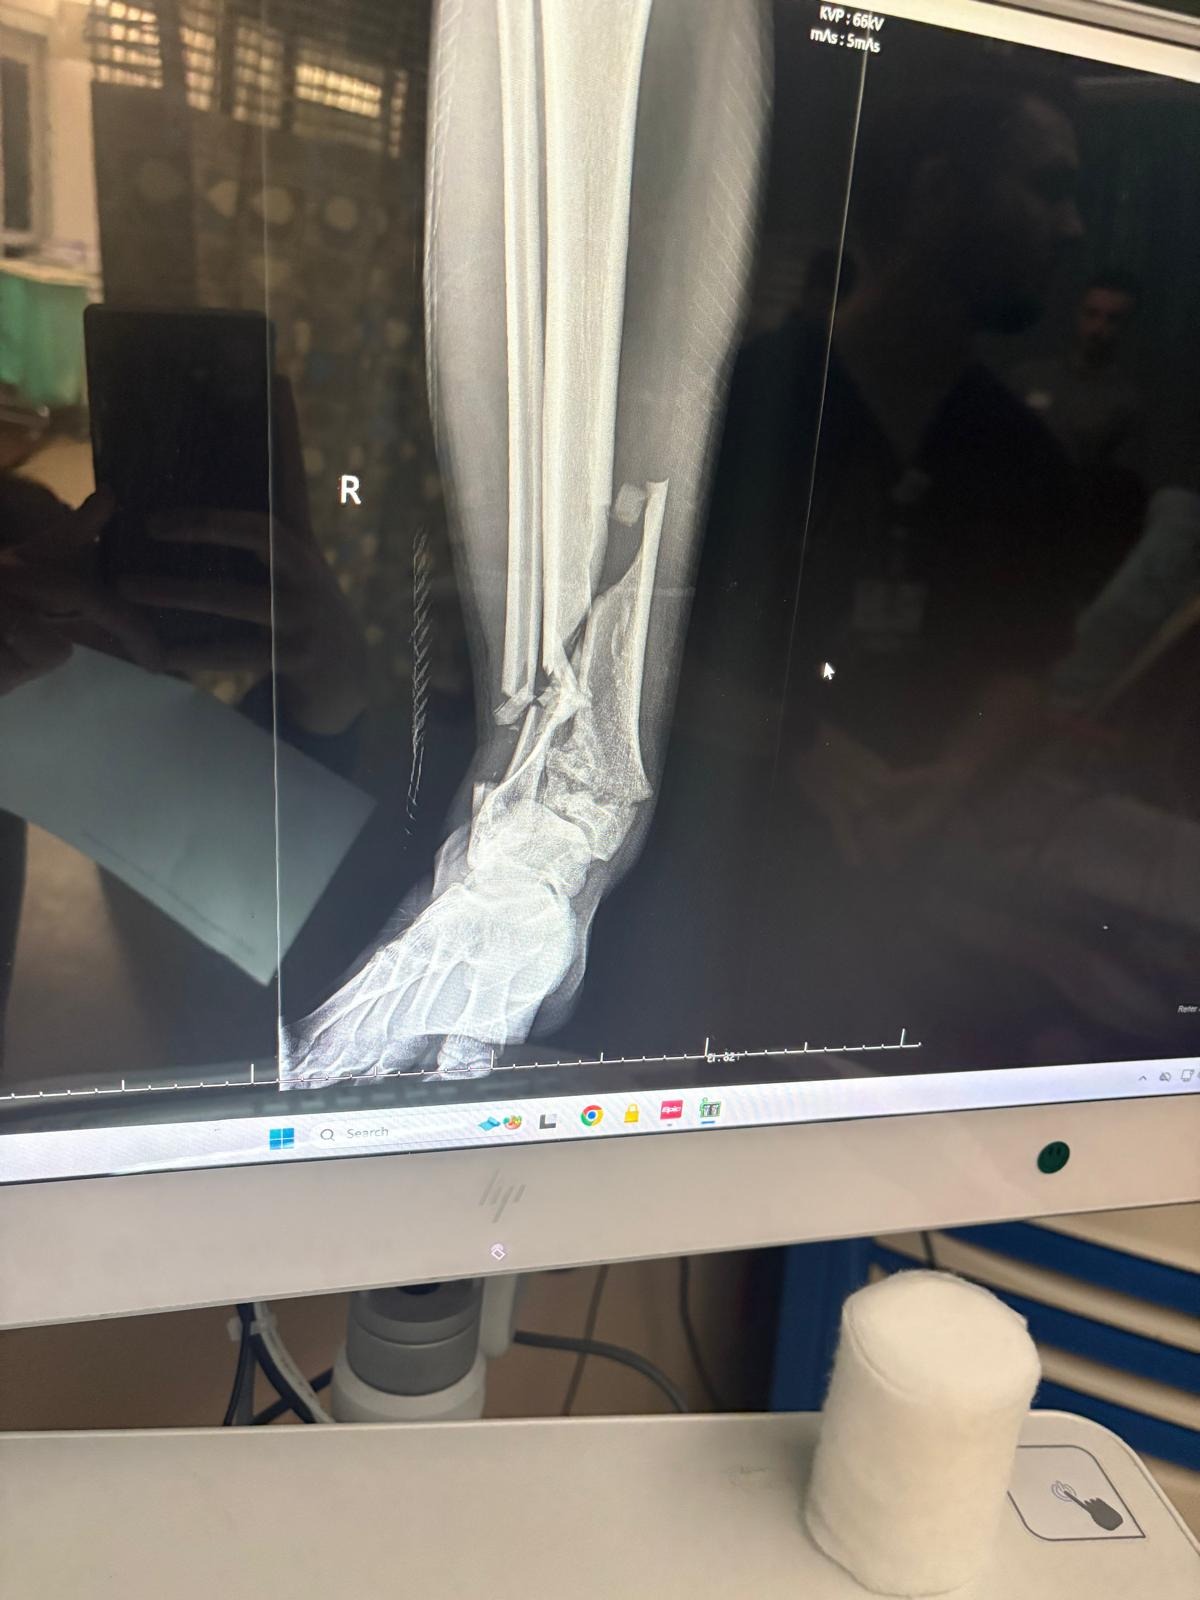

Marcelo and I have been married for less than a year. Recently, he suffered a serious accident while climbing, falling from a significant height. Considering the severity of the fall, it feels nothing short of a miracle that his injuries were limited to his ankle. Unfortunately, the impact shattered it, and due to the seriousness of the injury, he will need multiple surgeries followed by a long and demanding rehabilitation.

Marcelo y yo llevamos menos de un año de casados. Recientemente, sufrió un grave accidente mientras escalaba, cayendo desde una gran altura. Considerando la magnitud de la caída, sentimos que fue casi un milagro que sus lesiones se limitaran únicamente al tobillo. Sin embargo, el impacto lo dejó gravemente fracturado y, debido a la gravedad de la lesión, necesitará varias cirugías y un largo proceso de rehabilitación.